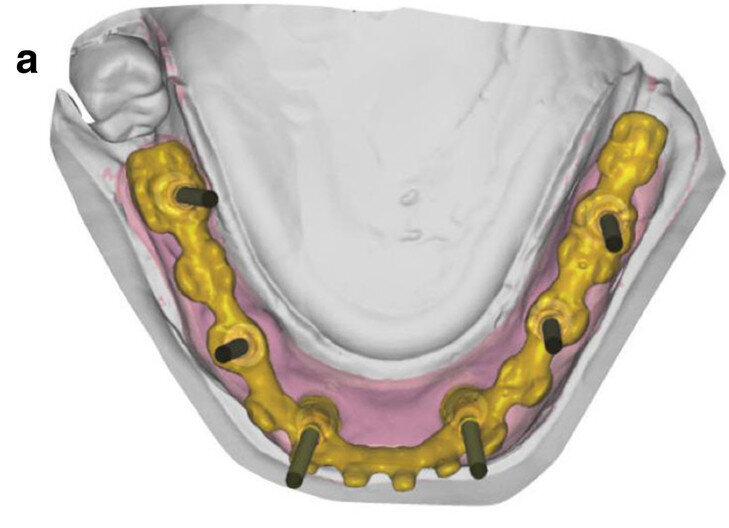

Fig. 5a: CAD/

CAM-fabricated surgical guides: tooth- and mucosa- supported (a) and implant- and mucosa-supported (b).

Fig. 5b: CAD/

After extraction of the painful and extremely mobile teeth #41, 31 and 32 and adaptation of the existing RPD, a cone beam computed tomography scan (PaX-Uni3D, VATECH) with a 5 x 8 cm field of view, 85 kVp generator voltage, 5.5 mA generator current and 0.2 mm voxel size was performed to proceed with the detailed implant planning (Fig. 4). Based on the anatomical conditions and prosthetic planning (i.e. tooth set-up for the provisional RPD), six implants were virtually planned (3Diagnosys, 3DIEMME) in positions #46, 44, 42, 33, 35 and 36. As the implant positions #42 and 33 interfered with teeth #43 and 33, a two-step procedure with two surgical templates was planned for the guided implant placement (Figs. 5a & b). The templates were fabricated stereolithographically (DS3000 and XFAB, DWS) according to the virtual implant planning. Based on the same digital file (Figs. 6a–c), a provisional fixed dental prosthesis (FDP) was prepared preoperatively, allowing for an intra-oral adaptation between the abutments and the framework in order to achieve a passive fit (Figs. 7a–d).